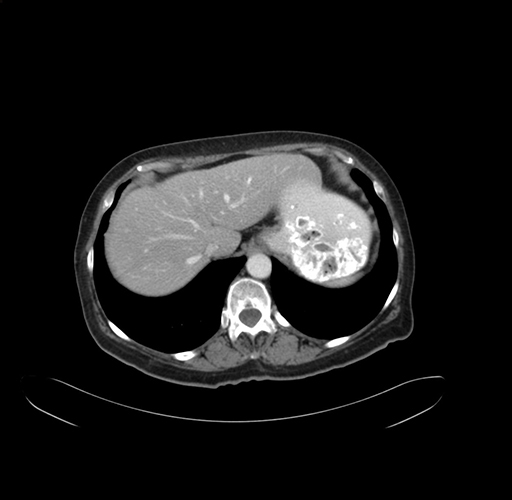

Pre-Chemo: Axial Venous